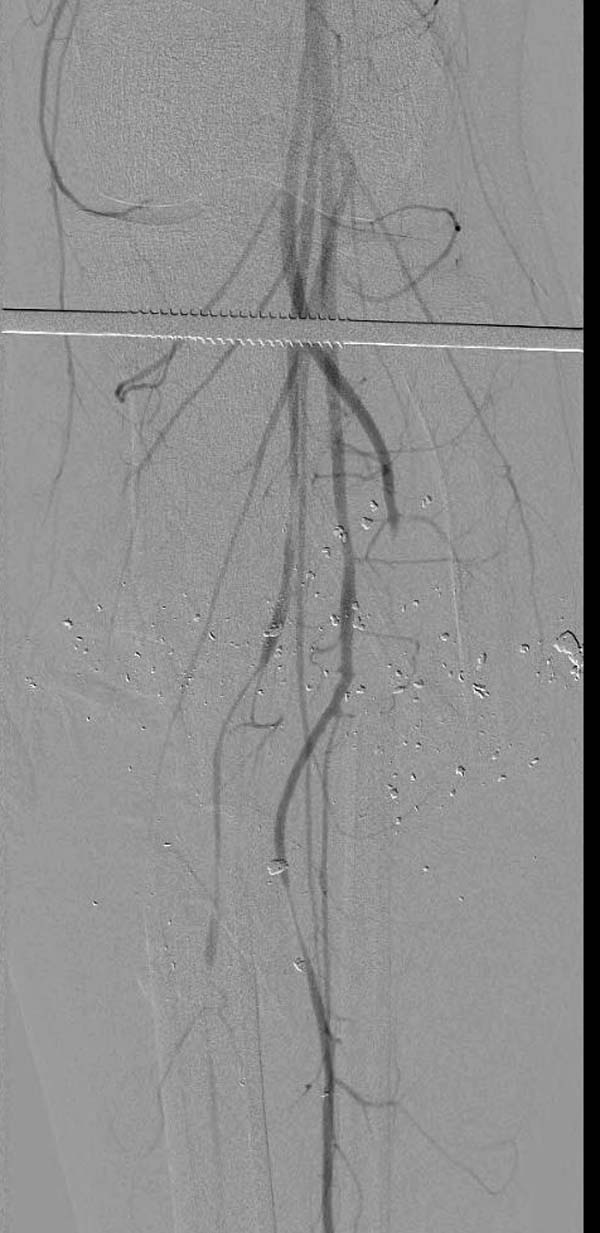

Имя     : 6 gsw tibia abgiography.jpg

Url     : http://weborto.net:8080/pipermail/ortho/attachments/20150717/eea7e369/attachment-0021.jpg